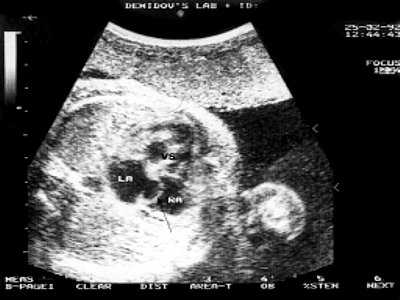

Рис. 1. Четырехкамерное сечение сердца плода в 30 недель гестации. Опухоль сердца прорастает миокард задней стенки левого желудочка, межжелудочковую перегородку. Межпредсердная перегородка уплотнена, овальное окно не функционирует (стрелка).

LA - левое предсердие, RA - правое предсердие, VS - межжелудочковая перегородка.

В 29 недель беременности отмечен значительный рост опухоли, распространенность процесса затронула стенки аорты, створки митрального клапана и межпредсердную перегородку. К моменту рождения опухоль вызвала формирование аортального и митрального стенозов, проросла в межпредсердную перегородку, вызвав преждевременное закрытие овального окна (рис. 2).